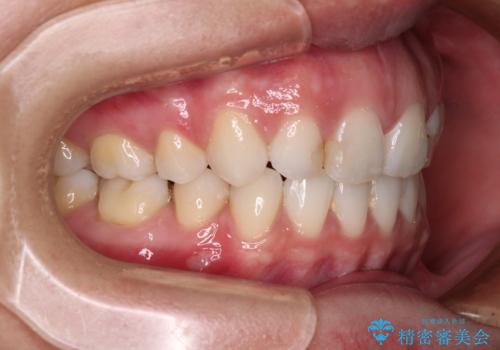

- くちばしのような前歯の突出感を気にして来院された患者様です。

上下左右第一小臼歯4本を抜歯して、積極的に口元を引っ込めるよう、ワイヤー装置にて矯正治療を行うこととしました。

抜歯矯正を行ったことで、顎先のつっぱり感や口元の閉じにくさを解消することができました。